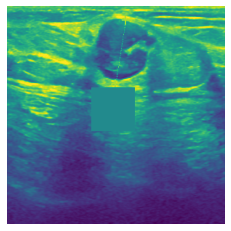

In figure 3, we present qualitative examples of different masking strategies. It is observed that, unlike context prediction and restoration, our method tends to propose targeted masks like the tumor regions or regions with abnormalities and avoids masking less helpful regions. However, it should be noted that Intelligent-Masking does not necessarily mask the tumor regions but considers all areas of interest that results in better feature learning. Examples of other masking samples are provided in supplementary materials. Furthermore, in medical images, unlike natural scenes, the structures are very local with imbalanced information throughout an image. Therefore, random masking strategies as shown in Fig 3 operate ineffectively by masking non-informative regions.

Figure 2: Qualitative examples of compared method’s strategies for masking

Figure 3: More qualitative examples of different distorting strategies including our method. We show the different self-supervised mechanisms on both datasets of MR (rows: 1-3) and ultrasound (rows: 4-6) images for lower-grade glioma and breast cancer diagnosis respectively. We include both images of normal (rows: 1,4) and cancer (rows: 2,3,5,6) conditions for each dataset. We also observe that our method treats each image based on its context information with no predetermined strategy.